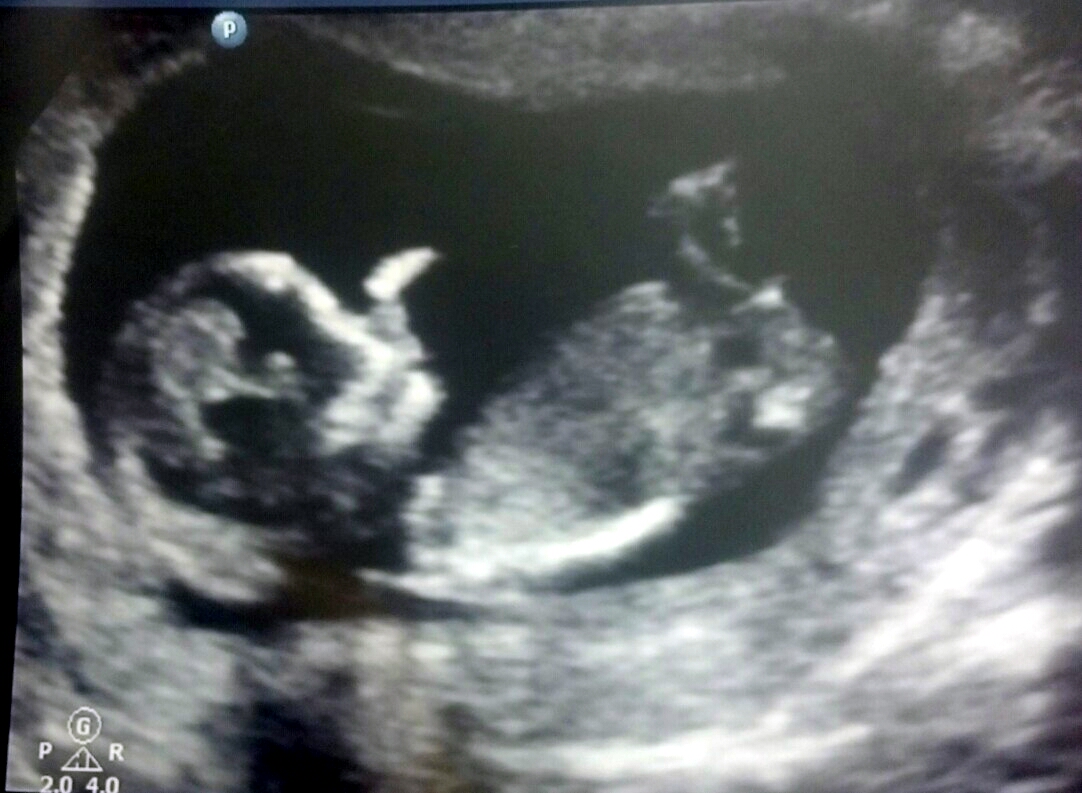

Attachment 12465 Attachment 12466

Really can't tell

Boy?

I would lean boy off of the short length and possible flick bit on the end:)